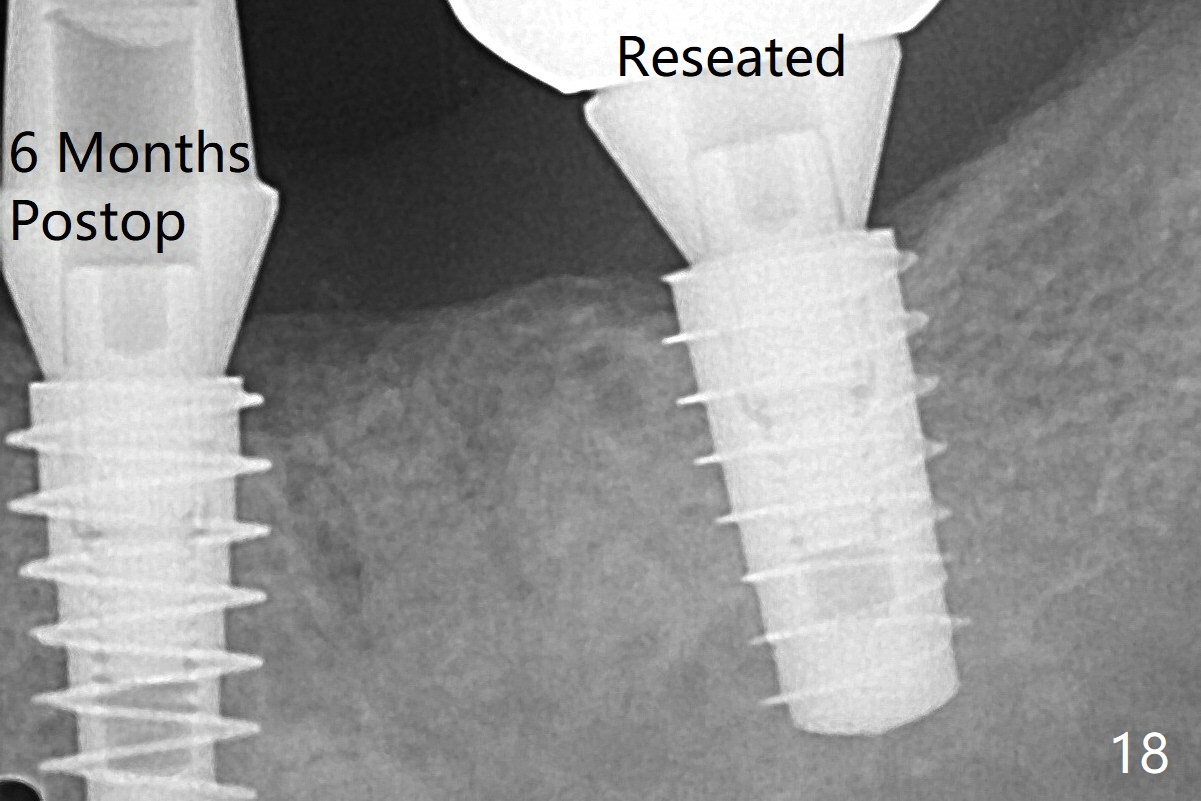

The incompletely seated abutment at #18 (Fig.5 <) is reseated completely 6 months postop.  Crestal bone forms distal to #19 implant.